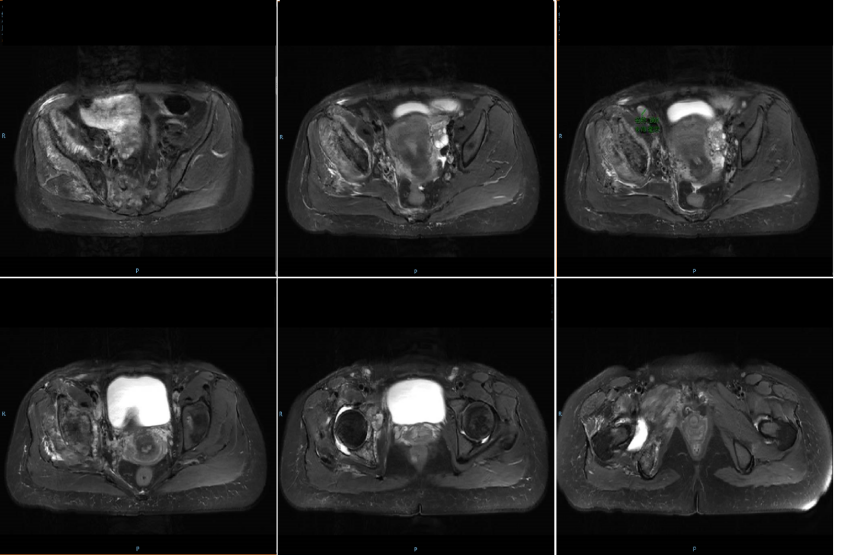

• 2021-08-20骨盆MRI:L3、L4、L5椎体及其附件、骶骨、双侧髂骨、双侧耻骨及右侧坐骨、股骨多发异常信号,考虑转移;右侧盆壁、骶前及双侧髂骨周围软组织内多发异常信号,右侧盆壁病灶内伴钙化,考虑转移;右侧髋部及股骨周围软组织肿胀,右侧腹股沟区多发肿大淋巴结,考虑转移。

骨盆.png

骨盆MRI

• 骨盆MRI:

2021-10-28:L4椎体、右侧髂骨周围软组织病灶较前(2021-08-20)缩小,余大致相仿。

2022-3-28:病灶较前大致相仿。